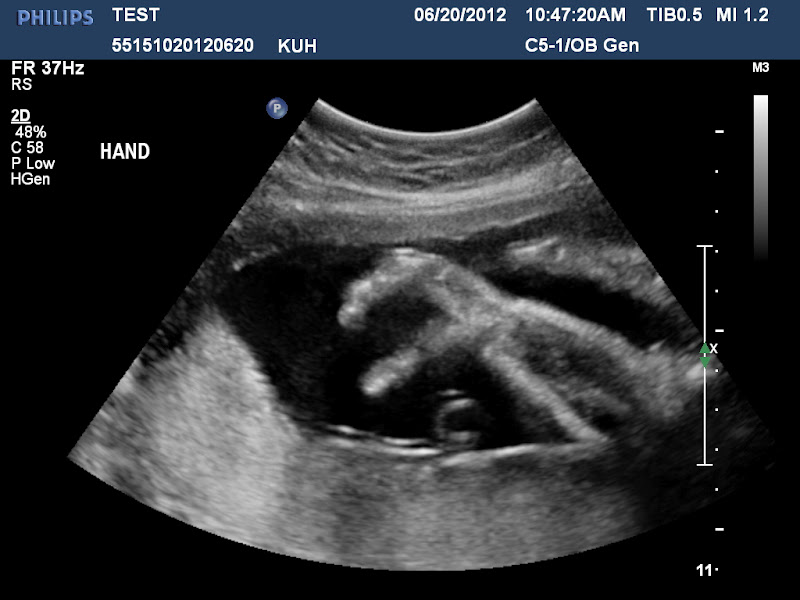

Yes, besides being uncooperative, she's apparently also going to be a bit of a drama queen - see the hand resting dramatically on her forehead? No thumb sucking at all today during the scan, like her big brother was typically doing during his ultrasound.